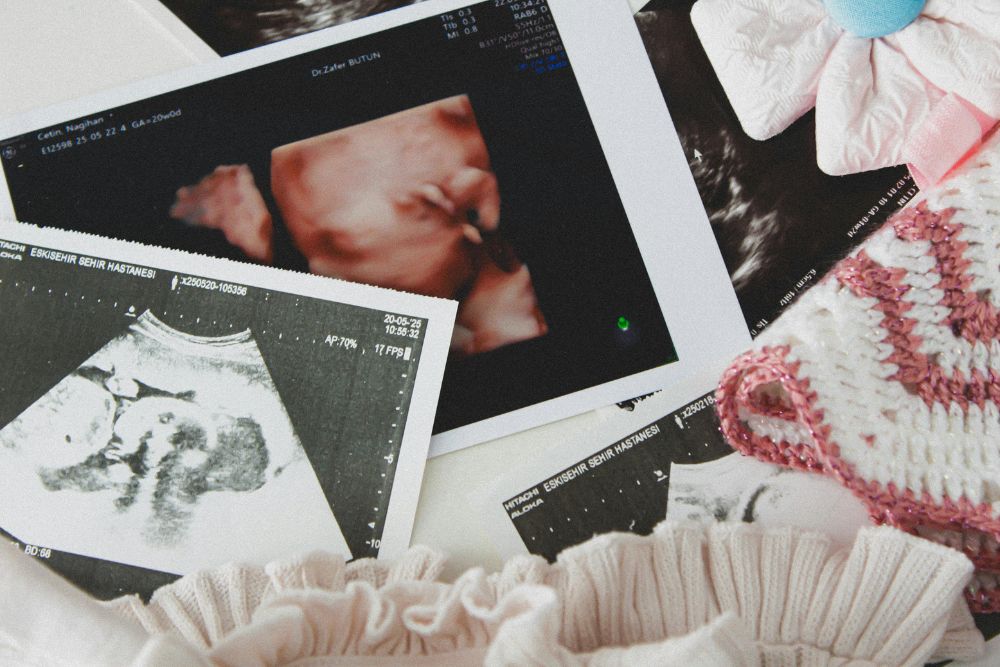

Le linee guida attuali prevedono che tutte le donne, indipendentemente dall’età, vengano informate sulla possibilità di effettuare test di screening come il test combinato (tra 11+0 e 13+6 settimane) o il test del DNA fetale su sangue materno. Non si tratta di esami obbligatori, ma di opzioni che devono essere offerte attraverso un counselling chiaro e completo, per permettere una scelta consapevole.

- Un’ecografia nel primo trimestre (entro 13+6 settimane), utile per datazione, vitalità e primo inquadramento;

- Un’ecografia morfologica nel secondo trimestre (tra 19 e 21 settimane), fondamentale per lo studio dell’anatomia fetale.